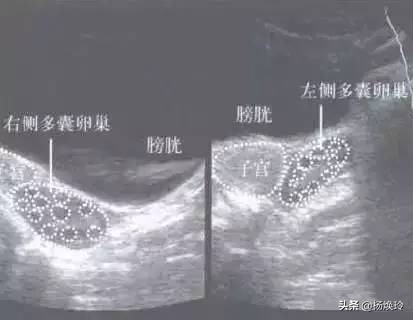

3,超声提示多囊。

超声提示多囊卵巢

多囊卵巢